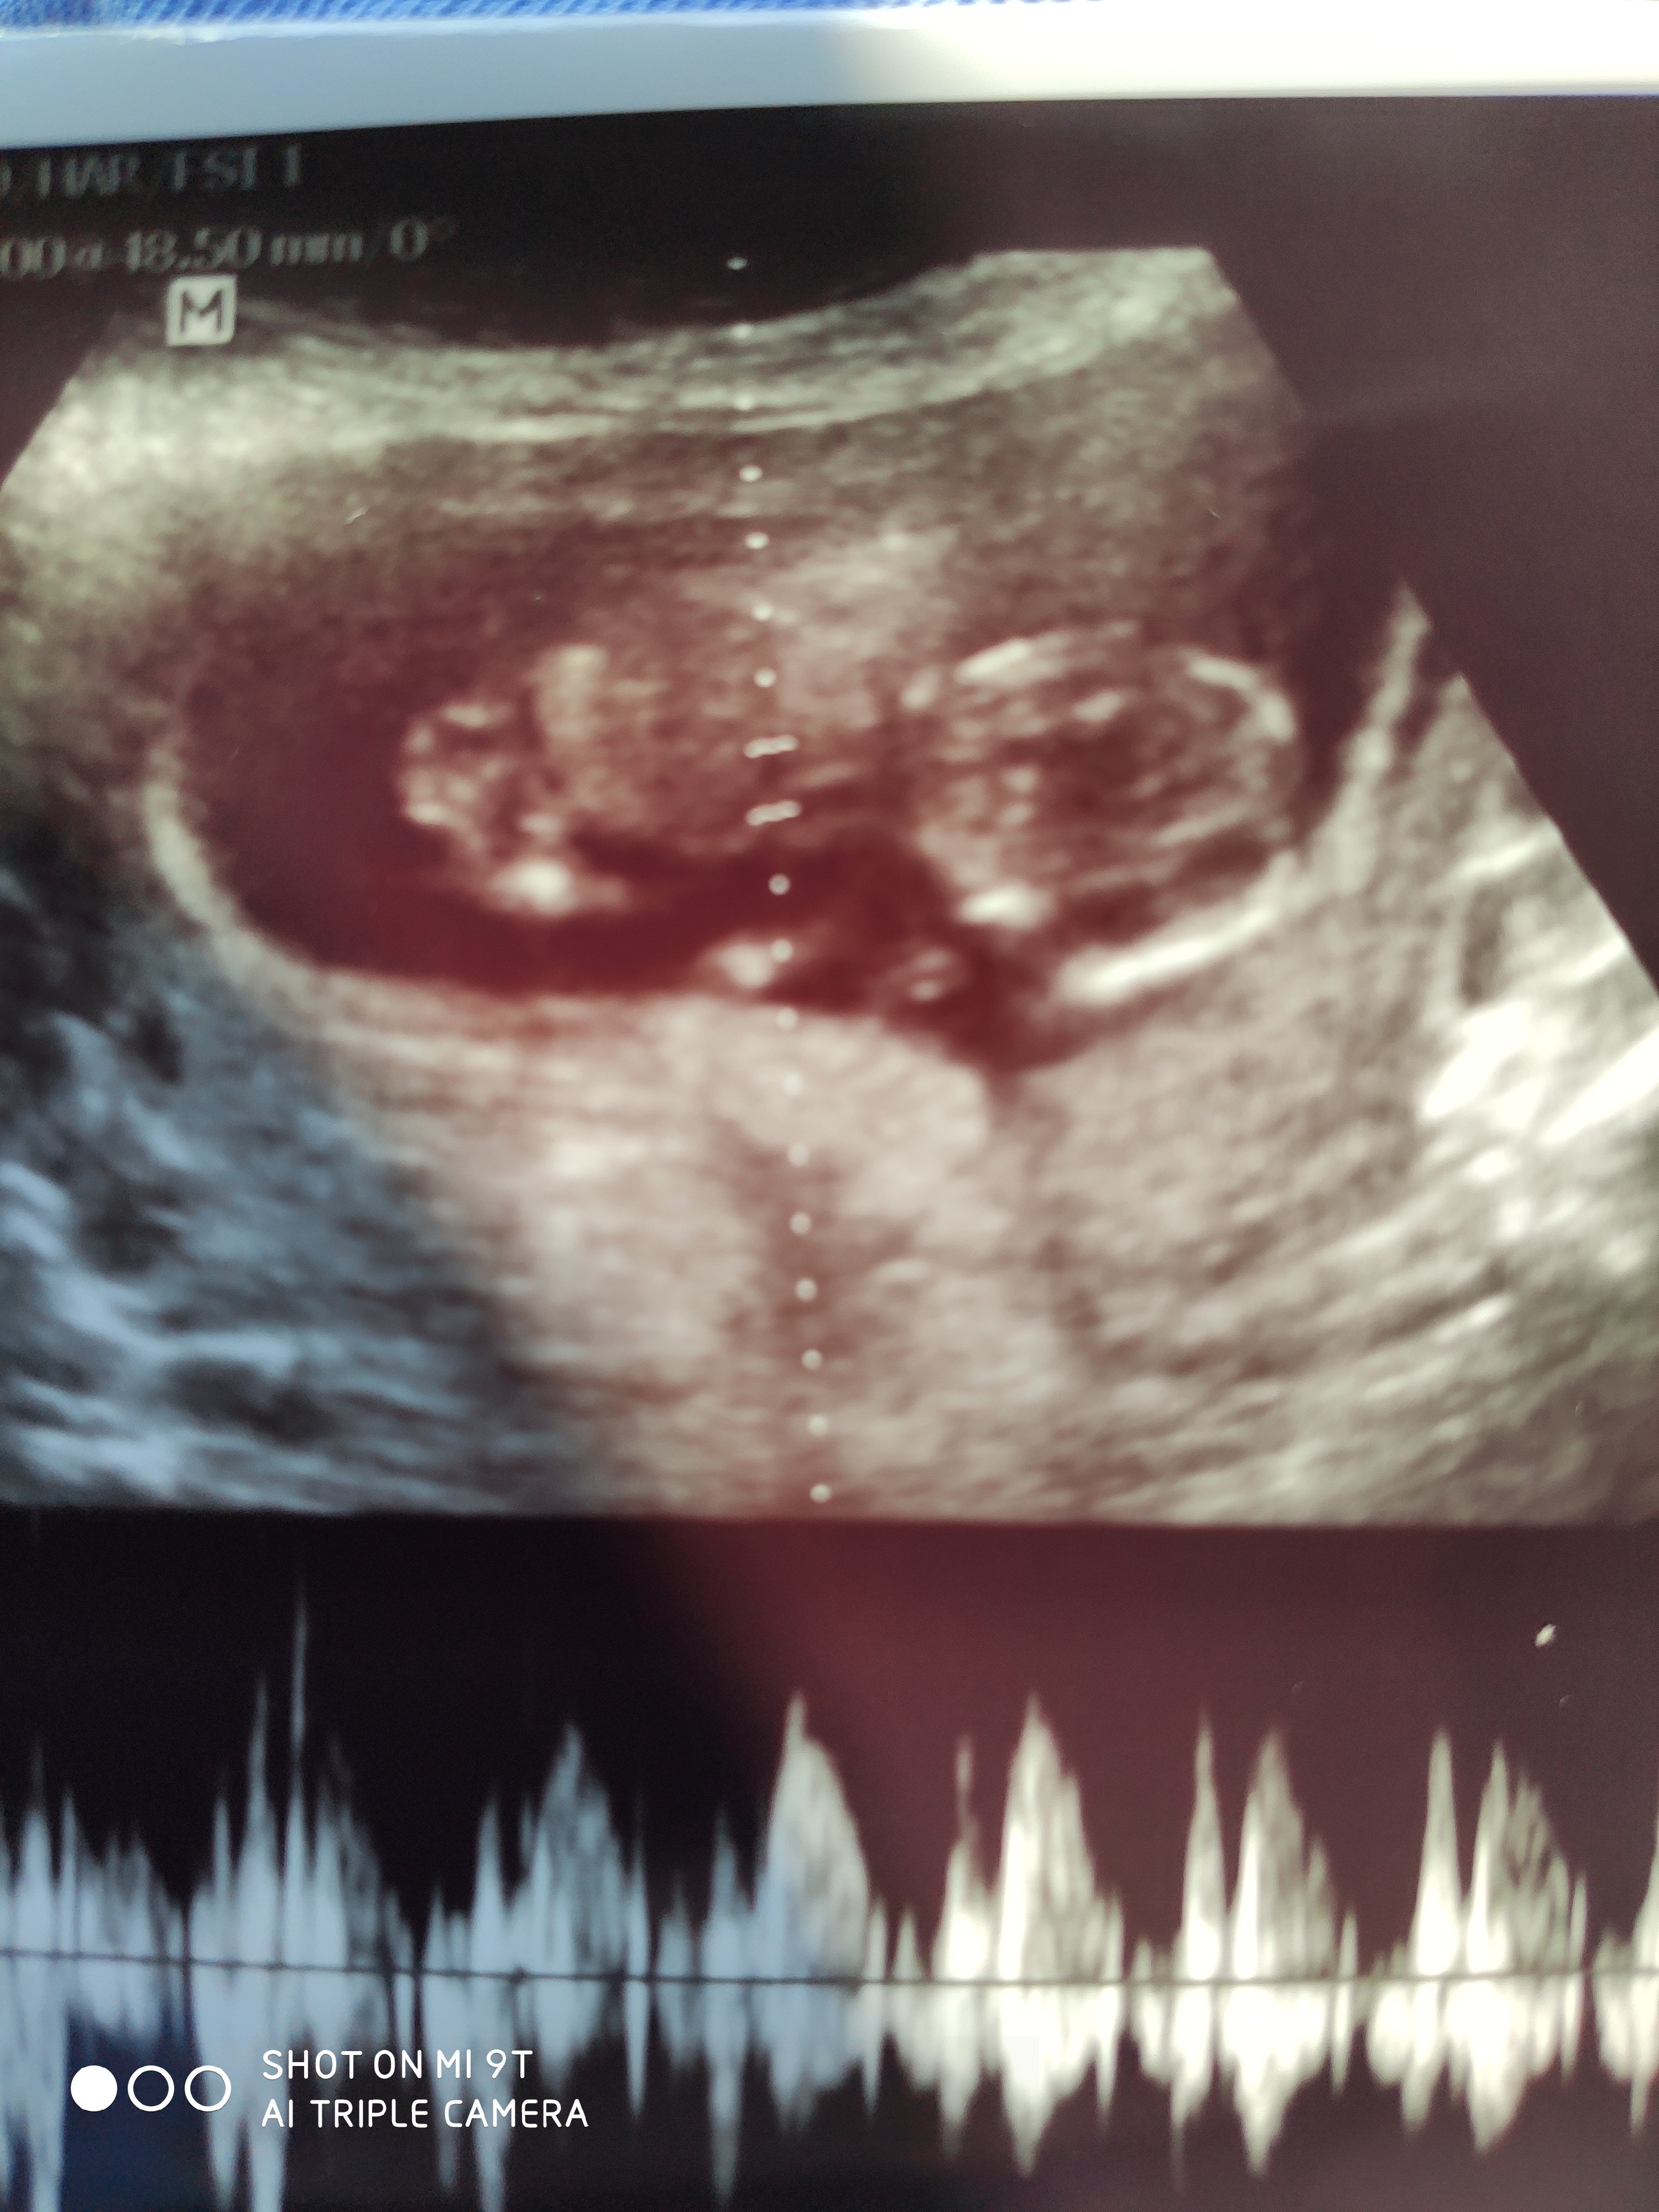

İşte kizlar iki adet sadece alabildik net görüntü yok diye

• 1628859272431..jpg

1628859272431..jpg

1.5 MB · Görüntüleme: 193